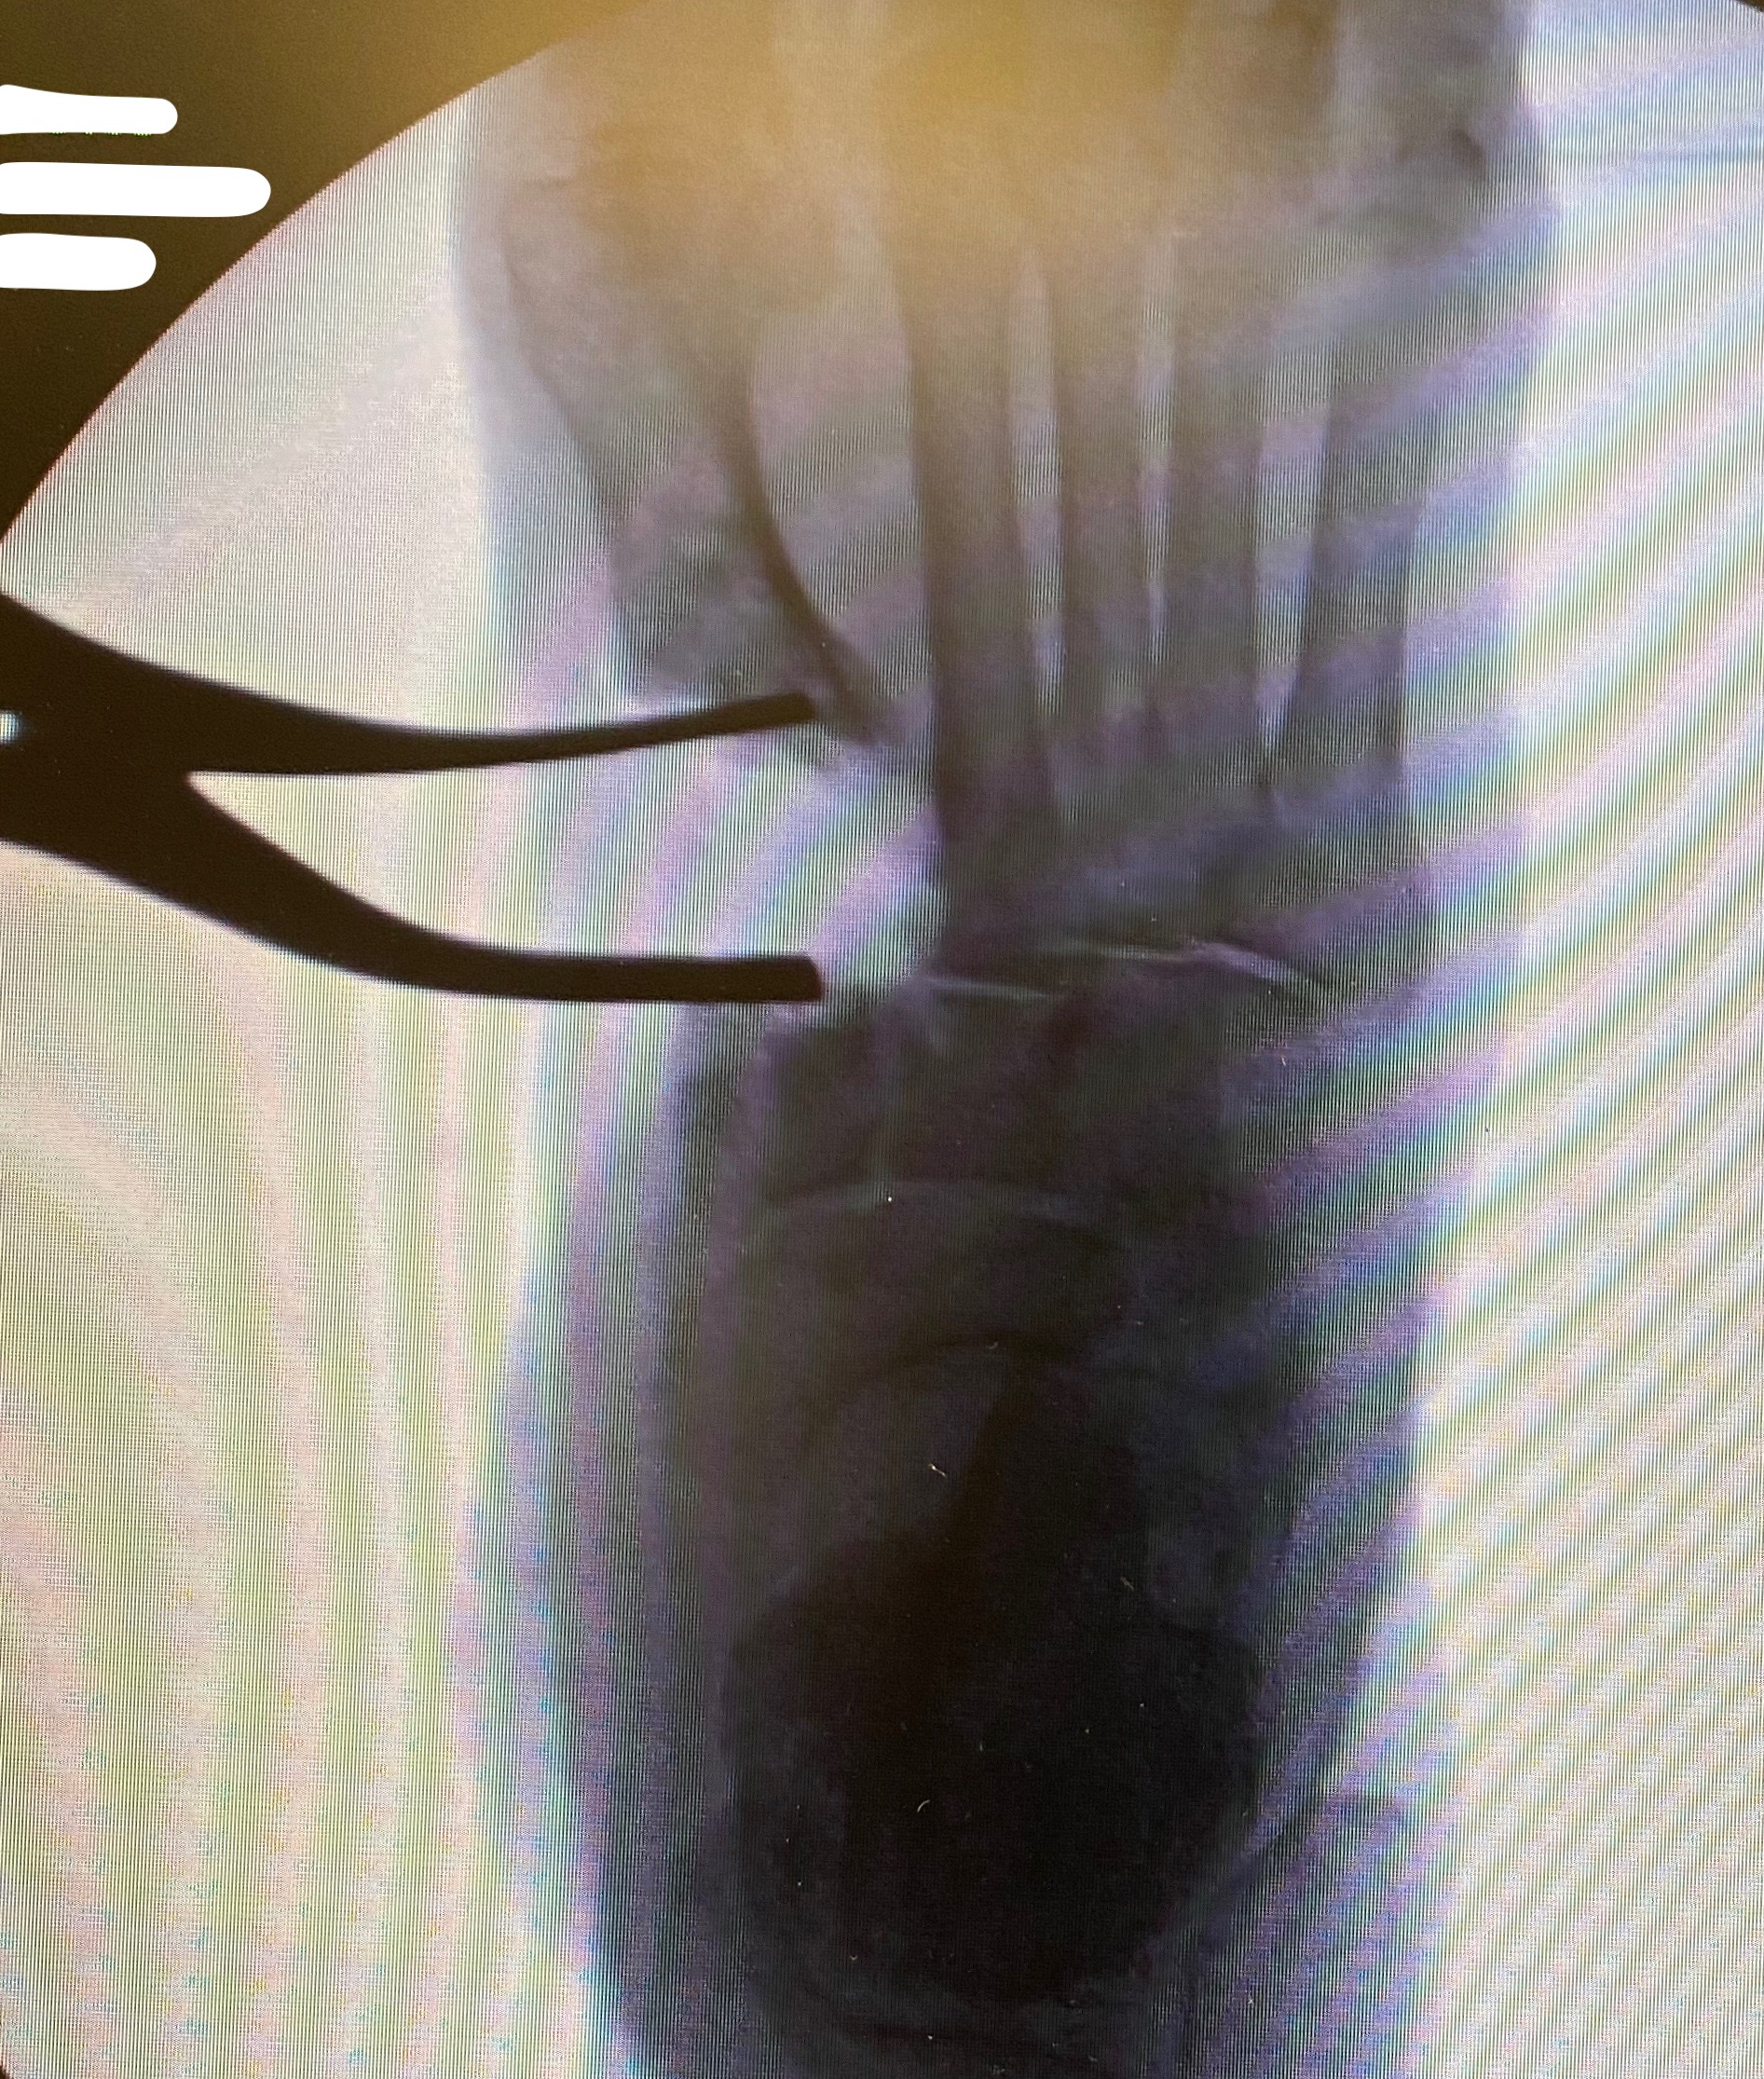

When it comes to harvest of autogenous bone from the posterior tuberosity of the calcaneus, surgeons most commonly utilize this harvest location for procedures in the midfoot and the forefoot.5 The calcaneus is a superior source of bone graft in terms of minimizing surgical time due to its close proximity to the primary surgical site. Calcaneal bone graft is a particularly useful compliment to arthrodesis procedures and fracture repair within the forefoot and the midfoot.

Biddinger and colleagues report that one can harvest up to three, eight mm trephine cores with minimal complication risk.16 DiDomenico and coworkers reported harvest of three to five cm3 of bone from the calcaneus using corticotomy and curettage while adding only two to three minutes of surgical time.17 The risk of sural nerve damage is low with the experienced surgeon but one should take care to avoid irritation in this area.15 Disadvantages of calcaneal bone graft include fracture risk, insufficient quality of bone and postoperative incisional irritation from footwear.18 If the calcaneus is unable to provide a sufficient volume of bone graft, a more proximal site of harvest may be necessary.5 Cross and DiDomenico characterize the calcaneus as a safe harvest site.19

We often utilize autogenous grafting for “positional arthrodesis” procedures. A positional arthrodesis allows for optimal positioning and fixation while often leaving a gap or defect due to translating an abnormal or malaligned position to a more anatomic or aligned position. Often the optimal position does not allow for 100 percent bony contact without the risk of shortening or malposition, thus leaving the surgeon with a bony deficit. One may backfill these defects with autogenous bone graft and maintain adequate positioning. However, we recommend as much bony contact as possible while also obtaining optimal position and maximal stability.

Backfilling a fusion or fracture site allows one to limit the amount of shear-strain across the arthrodesis/fracture site. One can define shear-strain as the angular changes between two line segments. Too much shear or strain across a fusion site will result in failure of the fusion, but a construct that is too stiff can lead to failure as it may not allow enough micromotion to stimulate bony healing.23

For those who prefer maximal primary bony contact during fusion, it remains unclear if there are gaps between bony contact on a microscopic level. Backfilling with autogenous graft during positional arthrodesis facilitates bony spot welding across the fusion site. It allows for deformity correction with some bony contact between the fusion/fracture site while providing structural fixation across the fusion site with a biologically friendly environment. Shear-strain bone grafting allows micromotion to occur in a controlled fashion, thus maintaining position but allowing for increased vascularity and bony healing.24 Perren and colleagues found that primary and secondary bone healing occur at the same rate.24 This concept allows utilization of autogenous grafting not only for reconstructive procedures but also in the setting of trauma.